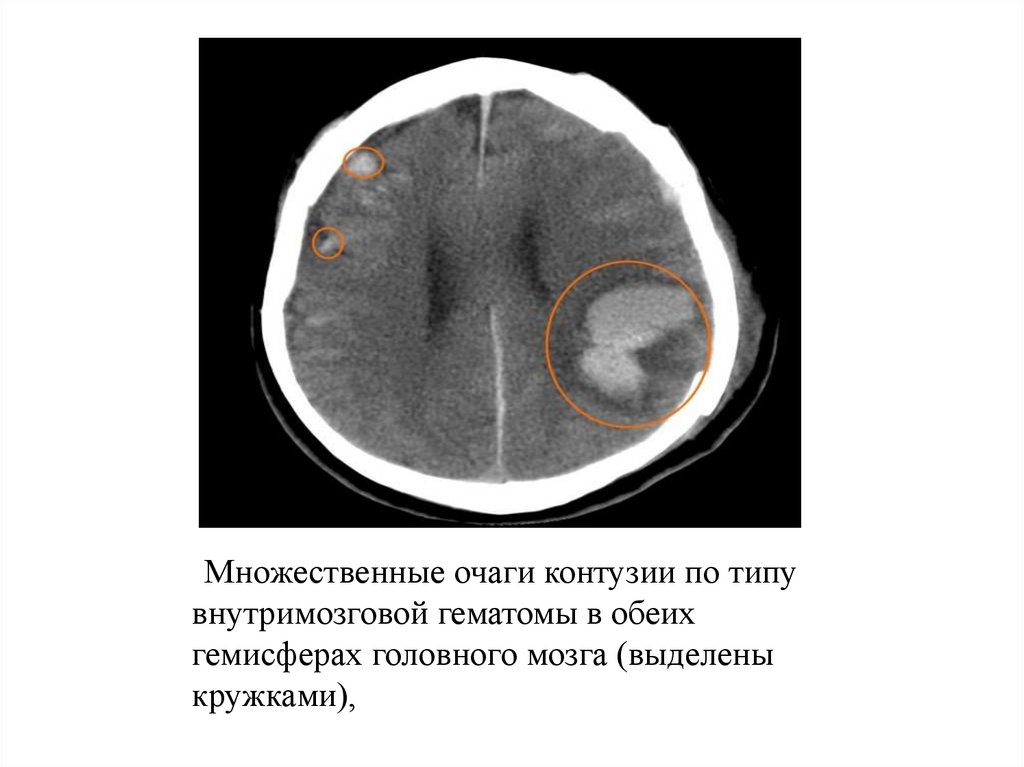

Множественные очаги контузии по типу

внутримозговой гематомы в обеих

гемисферах головного мозга (выделены

кружками),